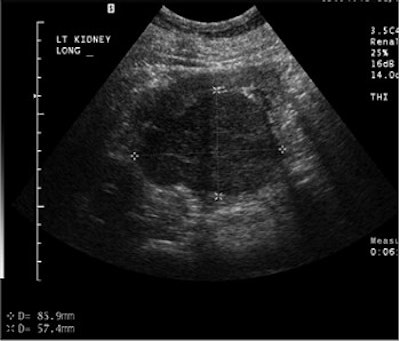

"Ultrasound with contrast has advanced over the years," Barr said. "We now have as many sequences ... as there are in MRI." At the time of these studies, the level of ultrasound technology that his group was using allowed them to inject contrast into a large renal cell carcinoma, and pick out the individual vessels in the cell. Also, the mass enhanced more than the normal renal cortex on ultrasound.

![]() |

A large renal cell carcinoma on pre-contrast ultrasound (above). After injection of the contrast agents (below), there is enhancement. Individual vessels in this renal cell carcinoma can be picked out; the mass also is enhancing more than the normal renal cortex. "If we increase the mechanical index, we can actually eliminate most of the parenchymal phase and actually look at discrete vessels," Barr said. Images courtesy of Dr. Richard Barr, Ph.D.